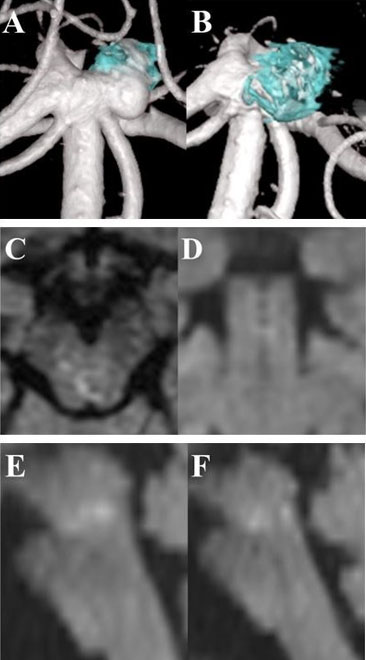

Gastroscopy was done under general anesthesia. In this procedure a gastroscope (GIF-H190; Olympus, Center Valley, PA, USA) and an esophageal overtube were used (Guardus Overtube; Steris, Mentor, OH, USA). Gastroscopy found a large amount of food bolus and blood clot in the dilated esophagus precluding further advancement of the gastroscope. The gastroscope was removed, and an overtube was fitted. The scope and overtube were then reinserted via the mouth and advanced to the esophagus to facilitate repeated passages of the scope. There was a large amount of organized clot and food in the entire esophagus. Due to this scope passage to the lower esophagus was not possible. Large clots with food were snared, suctioned, and manipulated to allow reasonable capture in repeated Roth Net passes (Figure 1). A combination of endoscopic suction, irrigation, snare use, and Roth Net use provided little improvement in clearance. Hence a nasogastric (NG) tube was inserted via the overtube into the oesophagus under direct visualization being following by the gastroscope (Figure 2). With adequate lubrication, the overtube can easily accommodate the standard gastroscope and an NG tube (Figure 3). The NG tube was connected to wall suction. The NG tube can be manipulated back and forth controlled at the site of insertion in the overtube to ensure adequate and—to some degree—targeted suction. With a combination of endoscopic irrigation and direct high suction with the NG tube, the food and clot were broken down and cleared effectively.

Figure 3: Insertion of the endoscope and nasogastric tube via the overtube.